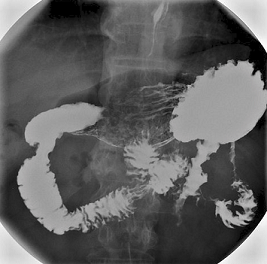

Barium meal

This is similar to a barium swallow. However, it aims to look for problems in the stomach and the first part of the gut (small intestine), known as the duodenum. These problems may include ulcers, small fleshy lumps (polyps), tumours, etc.

You drink some barium liquid but you then lie on a couch whilst X-ray pictures are taken over your tummy. It may take a little longer to do than a barium swallow.

So that the barium coats all around the lining of the stomach, the doctor doing the test (radiologist) may do one or more of the following:

Ask you to swallow some bicarbonate powder and citric acid before swallowing the barium. These 'fizz up' when they mix in the stomach and make some gas. (You may have the urge to burp.) The gas expands the stomach and duodenum and also pushes the barium to coat the lining of the stomach and duodenum. This makes the X-ray pictures clearer. It is the shape and contours of the lining of the stomach and duodenum which need to be seen most clearly on the pictures.

Ask you to turn over on to your stomach on the couch. Various X-ray pictures may be taken whilst you are in different positions.

You may be given an injection of a drug that makes the muscles in the stomach and gut relax.

Can I eat before a barium meal?

You will usually be asked not to eat anything for several hours before this test. (Food particles in the gut can make it difficult to interpret the X-rays). However, you may be allowed sips of water up to two hours before the test.

Barium meal stomach X-ray

By Lucien Monfils (Own work) via Wikimedia Commons